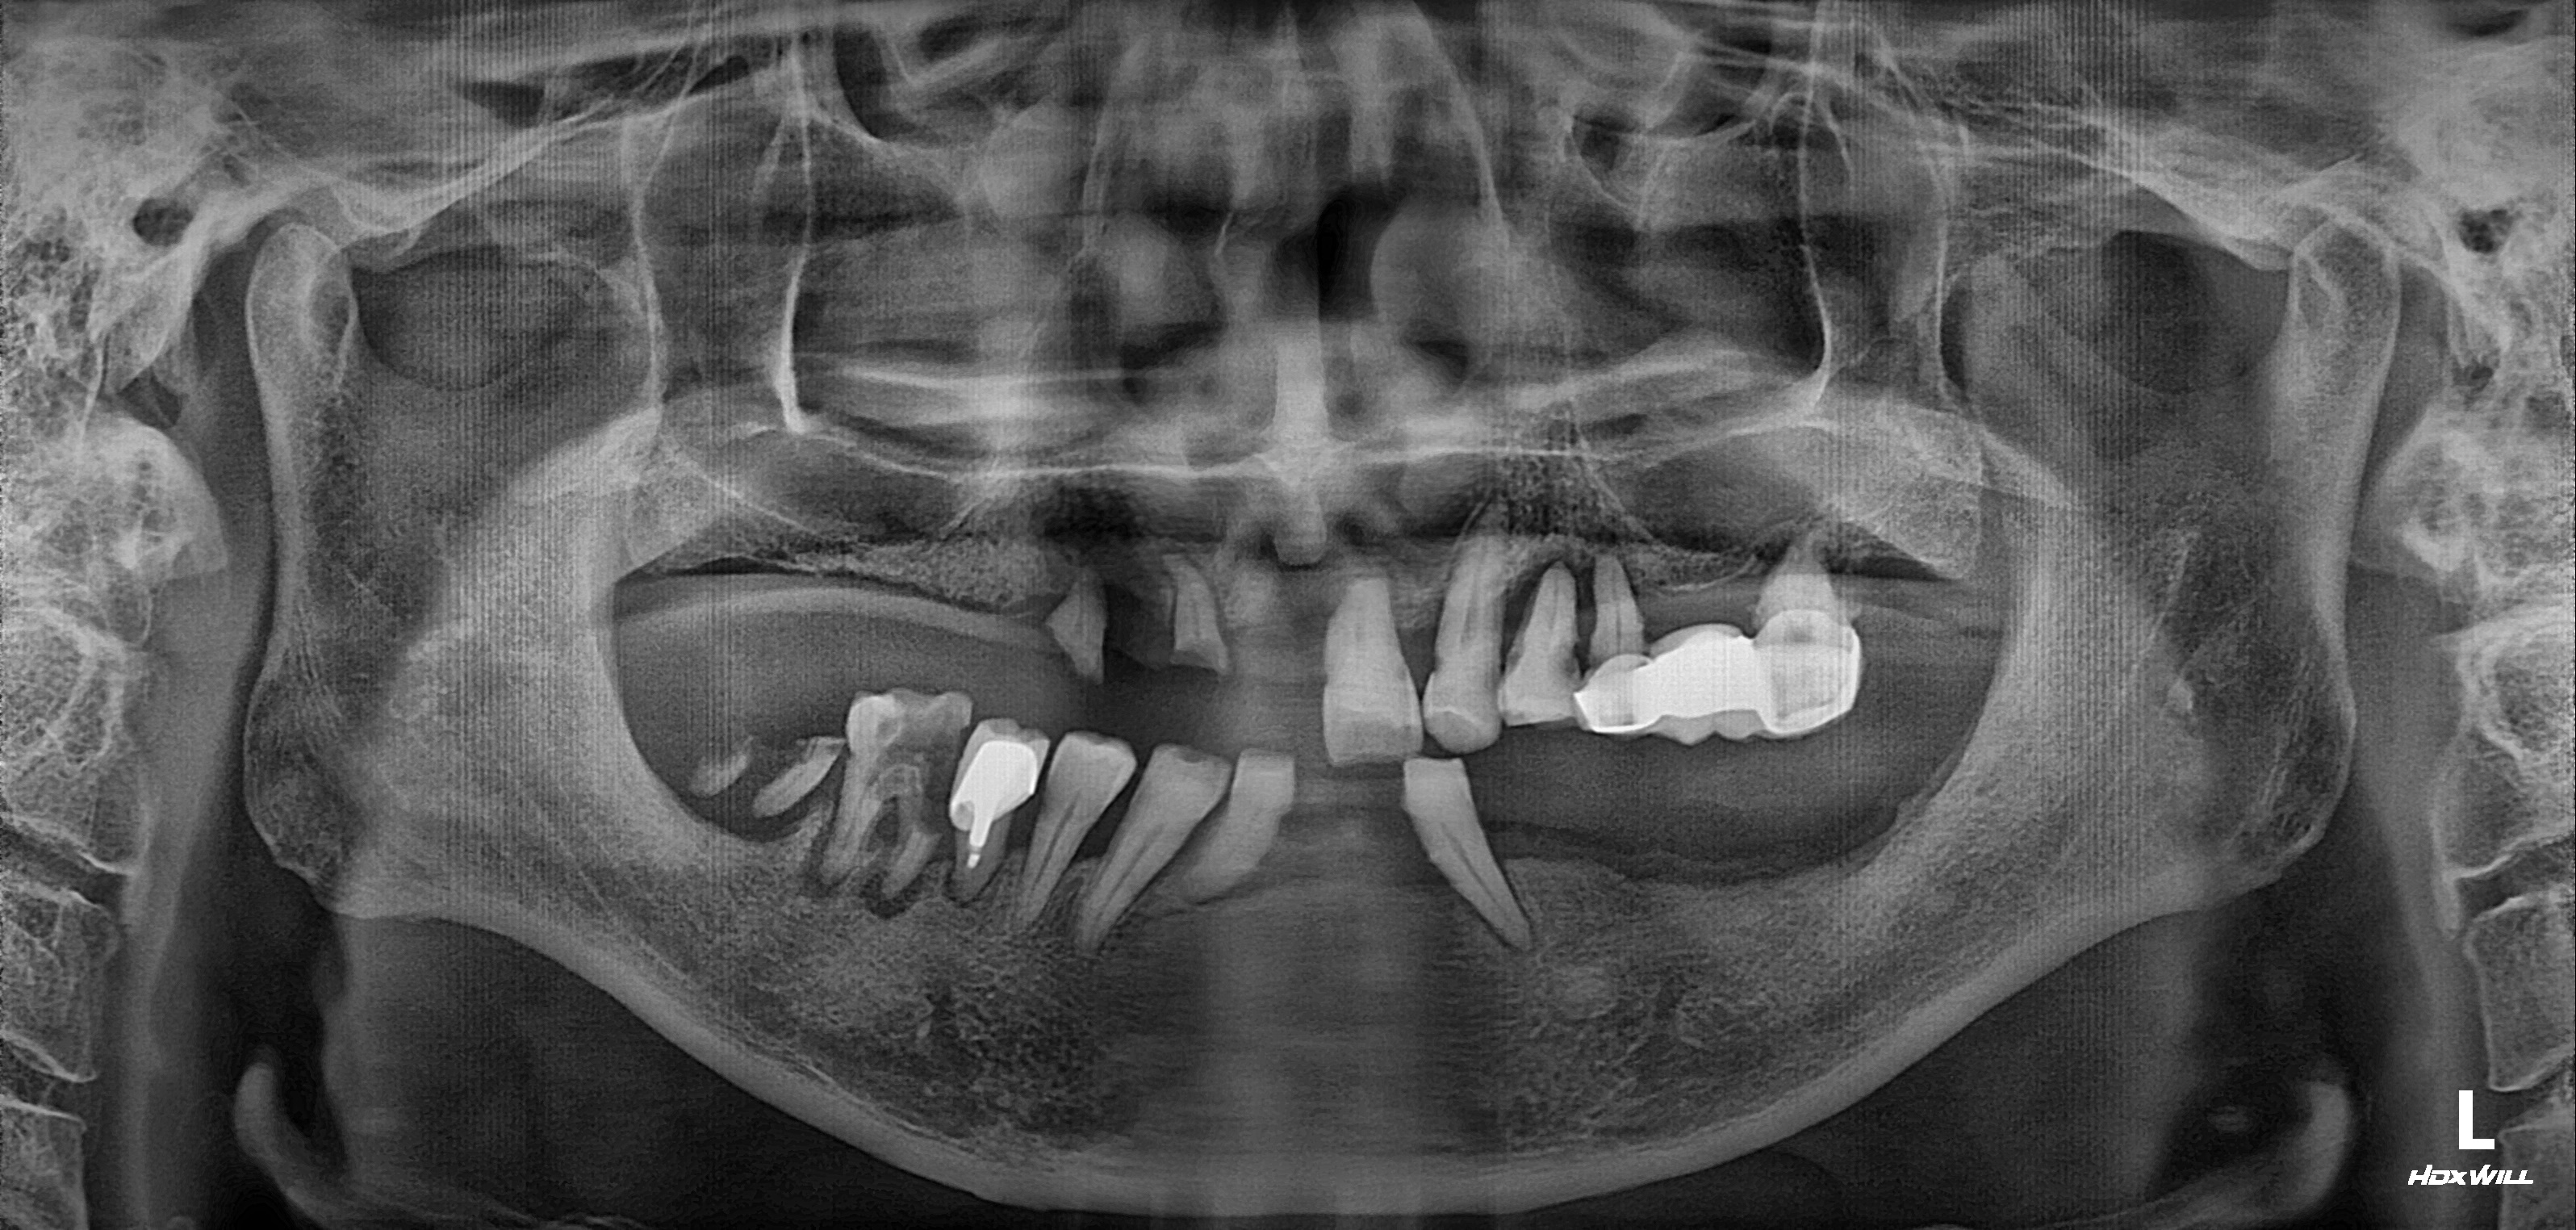

수술 전

수술 후

하악 임플란트 식립사례

전후사진